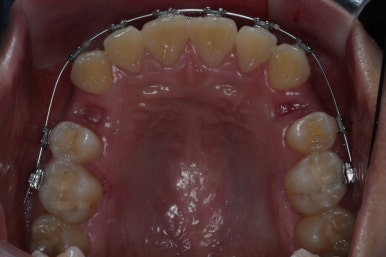

이제 가지런하게 하는 작업은 거의 종료되었고, 향후의 과정은 남은 이 뽑은 자리를 당겨주어 틈을 없애주면서도 입도 뒤로 좀 넣어주는 것이 되겠습니다.

위아래 아주 단단한 철사로 지탱해주면서 (앞니쪽에 고리가 달린 철사) 앞-뒤 치아를 서로 당겨주면서 이 뽑은 자리를 서서히 없애줍니다.

틈새를 모으는 작업을 반복적으로 행해주면 얼핏 봐서는 이뽑은 줄 모르게 치아가 서로 붙어있는 상황이 됩니다.